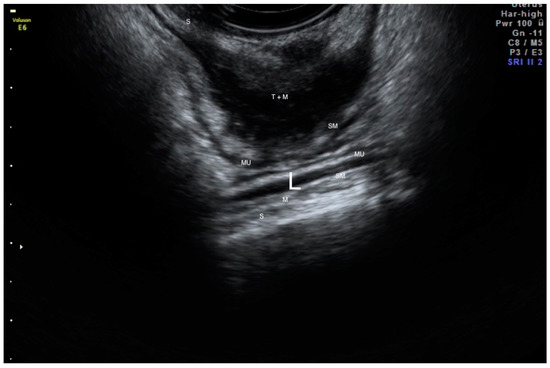

2.2. Ultrasound Measurements